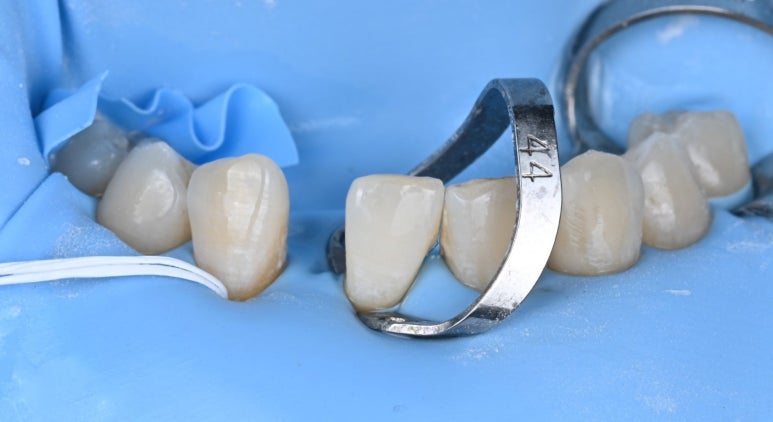

26.04.02 메릴랜드 브릿지 접착 준비

26.04.02 메릴랜드 브릿지 접착 후

26.04.02 치료 후 모습

26.04.02 치료 후